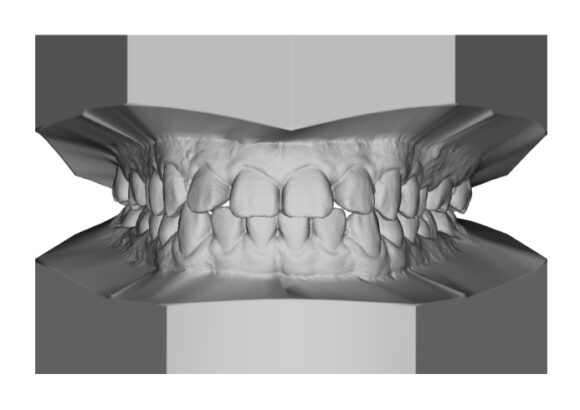

El escaneo dental es un dispositivo digital utilizado para capturar impresiones tridimensionales de la boca del paciente.

Este tipo de escaneo permite recrear la dentadura con una precisión que supera con mucho las muestras tomadas con materiales de impresión tradicionales.

• Réplica exacta de las estructuras dentales y tejidos adyacentes del paciente.

• Los escaneos son considerados tan precisos si no más exacto que los moldes de yeso. El proceso de escaneo es más cómodo para pacientes especialmente con reflejo nauseoso.

• Mayor precisión comparado con modelos convencionales de alginato, sin necesidad de repetir la toma de impresión.